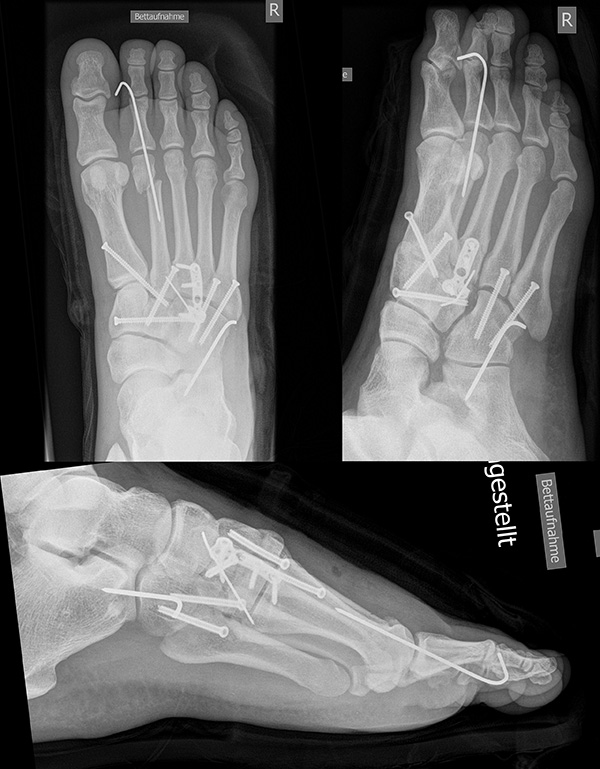

In der Regel werden die physiologisch rigiden TMT-1 bis 3 mittels Schrauben transfixiert. Hierfür werden meist kanülierte Kleinfragment-Kortikalisschrauben (3,5 oder 4 mm) verwendet. Diese können in Stellschraubentechnik von der Metatarsale-1-Basis in das Os cuneiforme mediale (Abb. 17) sowie vom Os cuneifome mediale in die Metatarsale-2-Basis und bei zusätzlicher intercuneiformer Instabilität vom Os cuneifome mediale in das Os cuneifome intermedium eingebracht werden.

Zum Lesen der Bildbeschreibung und zur Vollansicht bitte das Bild anklicken.

Ggf. wird zusätzlich ein K-Draht oder eine Schraube von der Metatarsale-2-Basis in das Os cuneiforme intermedium gebohrt (Abb. 18). Zur Transfixation der TMT-4 und 5-Gelenke werden, entsprechend ihres höheren physiologischen Bewegungsumfangs meist K-Drähte empfohlen. Die Indikation zur Transfixation wird von den meisten Autoren nur bei einer Instabilität gesehen, einige empfehlen eine Transfixation sämtlicher TMT-Gelenke unabhängig vom Ausmaß der Instabilität 10. Kleine, nicht refixierbare Fragmente sollten entfernt werden. Ist ein primärer Hautverschluss nicht möglich, erfolgt die temporäre Weichteildeckung mit Kunsthaut wie Epigard 112951710.

Wird die Entscheidung zur Arthrodese gefällt, sollten nur Gelenke mit einer symptomatischen Arthrose versteift werden. Meist genügt die Arthrodese der TMT-1 bis 3-Gelenke. Die Arthrodese kann mit Schrauben oder dorsalen Platten durchgeführt werden. Die betroffenen Gelenkflächen werden entknorpelt und das Gelenk mit einer Zugschraubentechnik oder einer dorsalen Platte stabilisiert (Abb. 19-22) 25 (Richter 2002; Richter 2007). Einige Autoren befürworten eine primäre Arthrodese auch bei rein ligamentären Verletzungen mit multidirektionaler Instabilität, da diese eine schlechte Heilungstendenz aufweisen und häufiger zu Korrekturverlust neigen 3617112.

Zum Lesen der Bildbeschreibung und zur Vollansicht bitte die Bilder anklicken.